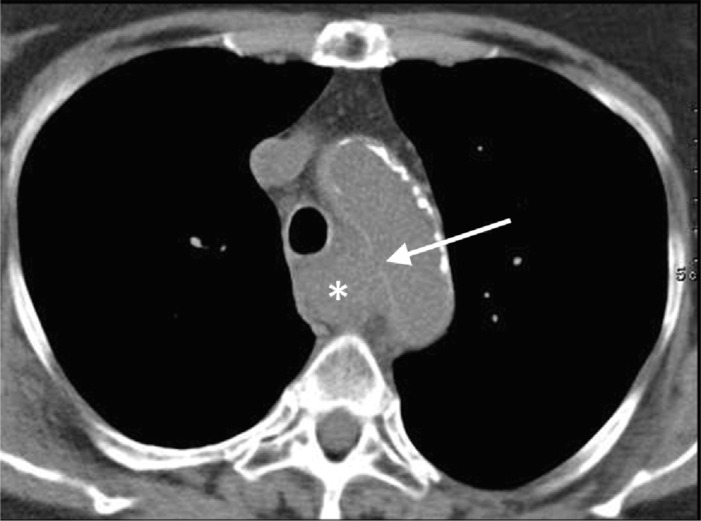

Aorto‑esophageal fistulas (AEF) are rare, often fatal connections between the thoracic aorta and esophagus, arising from aortic disease, esophageal conditions, or iatrogenic causes. Case: A 76‑year‑old woman, treated for esophageal nutcracker syndrome with endoscopic injection of botox, developed chest pain and esophageal hemorrhage. Computed tomography (CT) confirmed an AEF from an aortic pseudoaneurysm. She succumbed to circulatory collapse before treatment. Discussion: Endoscopic botox injections are a rare cause of AEF. The diagnosis relies on imaging and endoscopy, with surgery often required. Teaching point: Aorto‑esophageal fistulas are rare, life‑threatening complications, particularly after iatrogenic procedures. Early diagnosis is crucial, but prognosis remains poor.